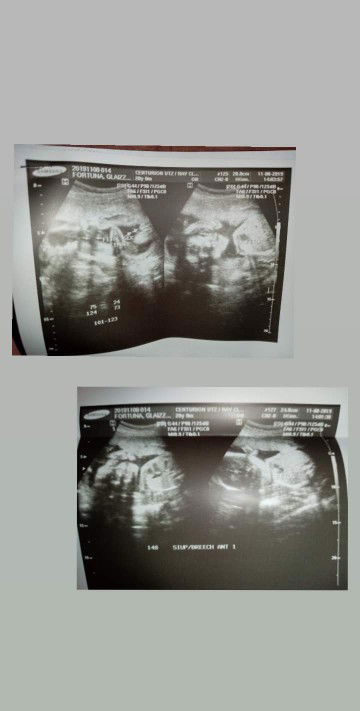

Team March 2020 EDD❤

March 6, 2020 here? what about yours?